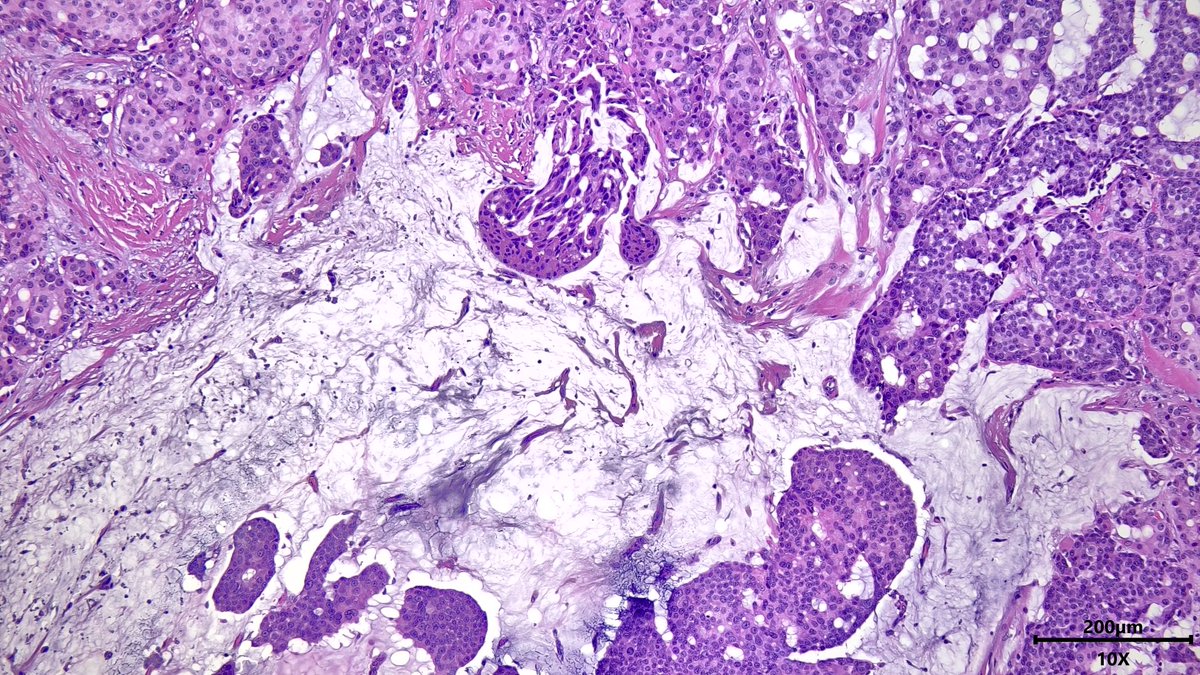

Case of Ductal Carcinoma In-Situ (DCIS) 🍪🔬 ☑️ Neoplastic epithelial proliferation confined to ducts and lobules ☑️ May show variety of architectural patterns, like solid and cribriform 👇 ☑️ Graded by nuclear atypia #PathX #PathTwitter #breastpath

Case of Malignant Adenomyoepithelioma ☯️🔬 This biphasic tumor can display malignant epithelium and/or myoepithelium within and extending from the lesion. This example👇 shows high-grade DCIS and metaplastic spindle cell carcinoma. #PathX #PathTwitter #breastpath